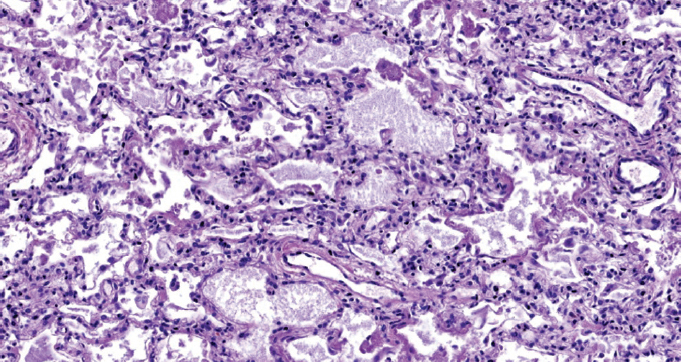

При патологоанатомическом исследовании — ткань легких с диффузными ателектазами, чередующимися с небольшими эмфизематозно расширенными участками, мелкоочаговыми кровоизлияниями в расширенные межальвеолярные перегородки (рис. 1). Большая часть альвеол звездчатой формы, очагово заполнены серозно-фибринозным экссудатом (рис. 2), слущенными альвеолоцитами, альвеолярными макрофагами (рис. 3). Часть альвеол выстлана гиалиновыми мембранами (рис. 4). Сосуды микроциркуляторного русла, расположенные в межальвеолярных перегородках, округлой формы, в просвете большей части которых определяются нити фибрина. Эндотелиальные клетки, выстилающие сосуды, набухшие, овальной формы, другие — более вытянутые, сохраненные не на всем протяжении стенки сосуда. Бронхи среднего и более крупного калибра звездчатой формы, стенка преимущественно утолщена за счет отека и склероза подслизистого слоя. Слизистая оболочка бронхов представлена цилиндрическим эпителием с дистрофическими изменениями, местами слущенным, в сохраненных участках с явлением пролиферации. В просвете бронхиол и более крупных бронхов выявляются десквамированный эпителий, единичные эритроциты, макрофаги. Кроме этого, преимущественно перибронхиально — диффузная лимфоцитарная инфильтрация с примесью умеренного количества нейтрофильных лейкоцитов; разрастание соединительной ткани, образование мелких единичных лимфоидных фолликулов.

Рис. 2. Альвеолы заполнены серозно-фибринозным экссудатом. Окраска гематоксилином и эозином. Ув. ×200 / Fig. 2. The alveoli are filled with serous fibrinous exudate. Stained with hematoxylin and eosin. Magnification ×200